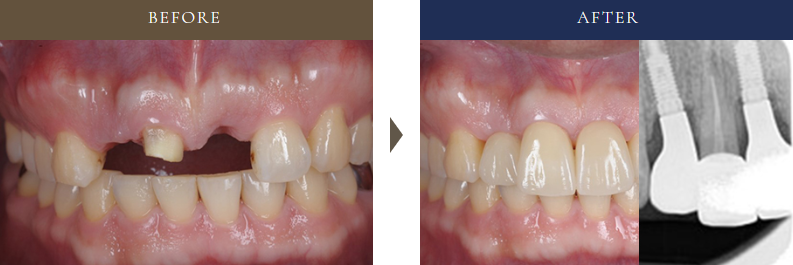

5-2:症例②|30代男性・前歯に2本インプラント(骨造成あり)

30代男性の前歯に2本のインプラントと骨造成を行った症例。審美性と安定性に配慮した治療のビフォーアフター。

• 治療内容:事故で前歯を2本失い、審美性と機能性の両立を目指してインプラント治療を実施。

• 治療期間:約8ヶ月

• 費用: 796,000円(税込875,600円)

• 補足:見た目の自然さにこだわり、隣の歯とのバランスも丁寧に調整。CT診断をもとに、安全かつ美しい仕上がりを実現しました。